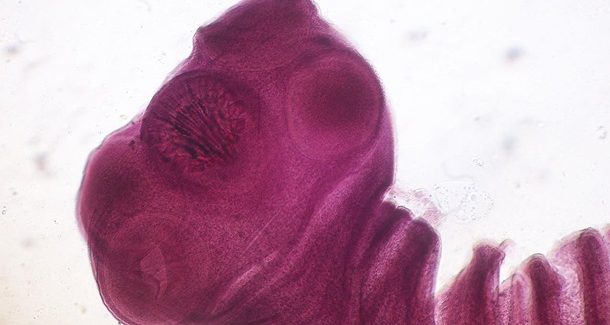

Свиной цепень может повергнуть к эпилепсии

Китайские доктора описали показательный случай цистицеркоза — отложения личинок свиного цепня в ткани головного мозга, что привело к припадкам эпилепсии, пишет N+1 28 ноября. Червь, вероятно, проник в организм пациента вместе с не до конца приготовленным мясом чушки или ягненка.

Жизненный цикл свиного цепня имеет несколько стадий. Если это цистицерк, то в кишечнике из него развивается полноценный червь, какой дальше начинает размножаться. Если это онкосфера, то она может мигрировать в разные части тела.